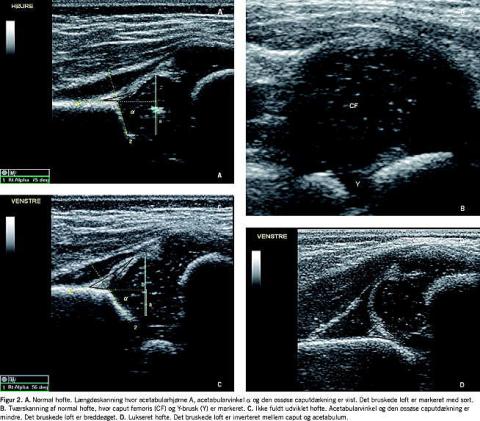

Hoften blev betragtet som normal (Figur 2A og B ), når alle morfologiske parametre var normale, og hoften var stabil. Ved normale fund blev undersøgelsen af barnet afsluttet.

Hofterne blev diagnosticeret som IFU (Figur 2C ) og således ikke behandlingskrævende, hvis børnene var yngre end 12 uger, selv om den første UL viste let dysplasi. Hvis en ny UL tre uger senere viste stabilitet og forbedrede morfologiske forhold, bibeholdt børnene denne diagnose, indtil hofterne normaliseredes.